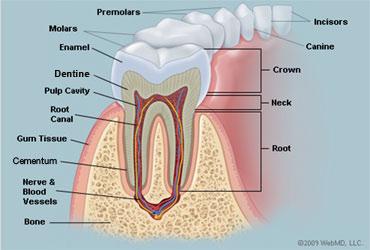

10

Rugae of the Hard Palate

11

Vestibule

12

Uvula

13

Deciduous Teeth

baby teeth

14

Permanent Teeth

15

Incisors (8)

Permanent Teeth FRONT

16

Canines (4)

Permanent Teeth

17

Premolars (8)

Permanent Teeth

18

Molars (12)

Permanent Teeth

19

Crown

20

Neck

21

Root

22

Alveoli

23

Gingiva

24

Enamel

25

Dentin

26

Cementum

27